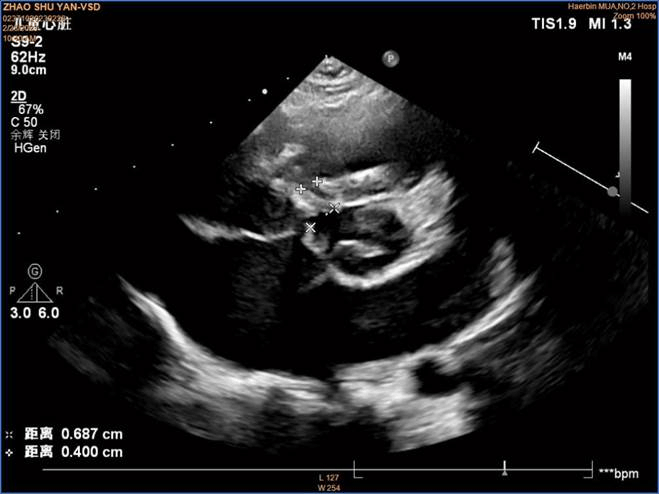

术前彩超

入院后经过全面检查发现心脏杂音,心脏超声证实室间隔缺损,缺损直径约为4.4 mm,确诊为室间隔缺损合并膨出瘤。自然闭合的可能性几乎没有,符合介入封堵手术治疗指征。

术后超声